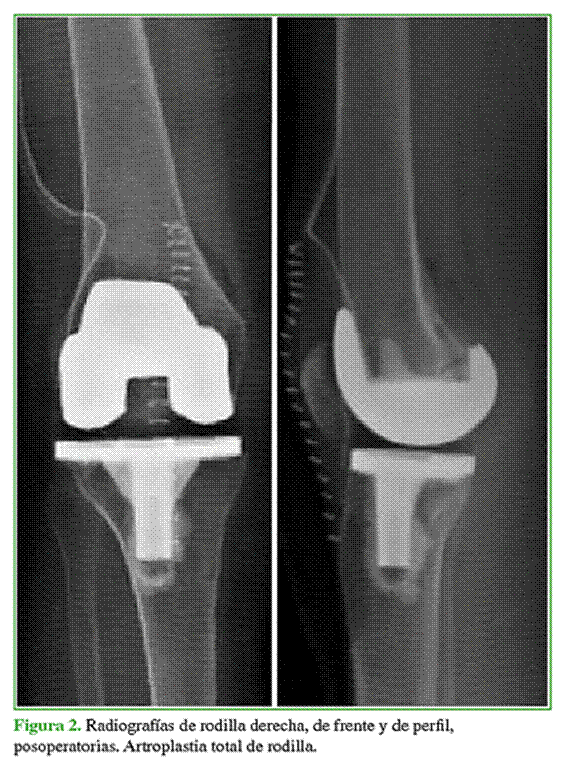

Mujer de 85 años, con diagnóstico de genu valgo derecho de 19° (Figura 1). Como antecedentes presentaba enfermedad de CREST, hipotiroidismo e hipertensión arterial. Se realizó una artroplastia total de rodilla (PFC® Sigma, DePuy, Leeds, Reino Unido) que duró 75 minutos, no hubo complicaciones intraoperatorias (Figura 2). No se utilizó manguito hemostático. A las 6 h del procedimiento, la paciente refirió un dolor intenso en la pierna y el pie, sensación urente con hipersensibilidad en el pie y cambios de coloración que duraron unos minutos y desaparecieron con agentes analgésicos. Inicialmente se sospechó una enfermedad de Raynaud por su enfermedad de base, pero fue descartada por el cuadro clínico. La paciente mejoró paulatinamente durante la internación y fue dada de alta.